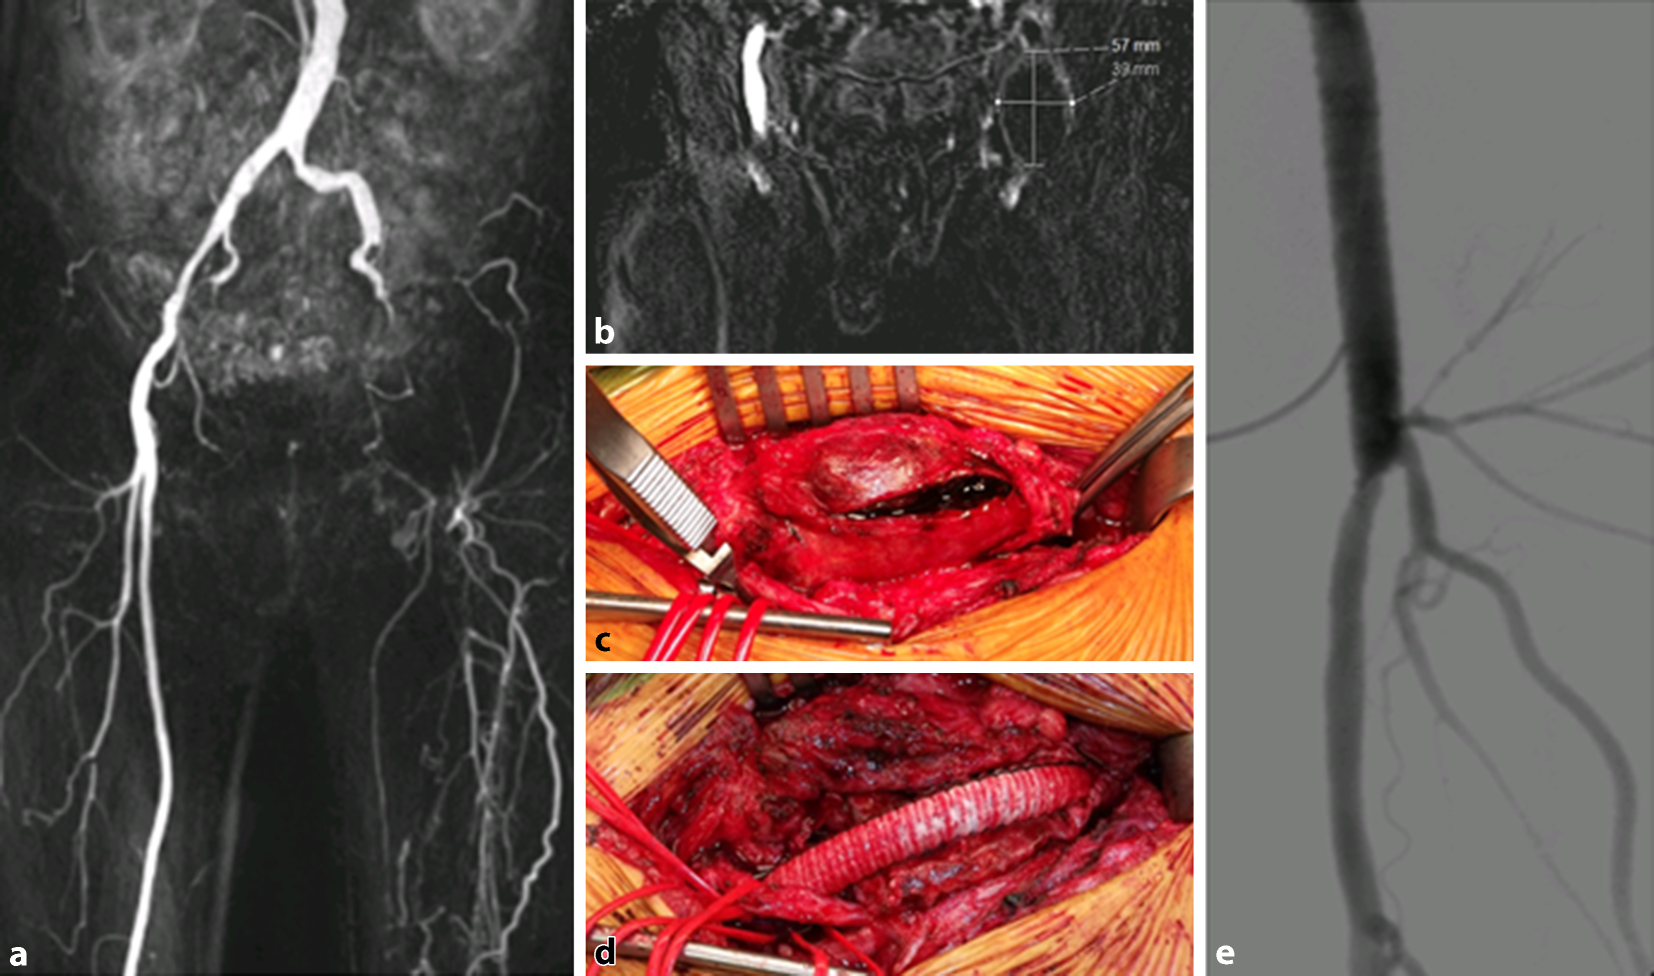

Hinsichtlich der Versorgung der Primär-NA ist in der Literatur eine Rezidivrate von 8,5 % bis 10,4 % beschrieben [6, 21, 24]. Eine Interponatanlage ist die Methode der Wahl im Rahmen der gefäßchirurgischen Rekonstruktion ([6, 9, 10, 20]; Abb. 4). Die erhöhte Rezidivrate bei der Aneurysmorrhaphie mit oder ohne Patch lässt sich am ehesten durch partielles/residuelles Belassen der aneurysmatisch veränderten Gefäßwand basisnah erklären.

Abb. 4

Beispielhafte Bildgebung bei einem repräsentativen Fall (klinisch: inkomplette Beinischämie links). a MR-Angiographie der Becken/Beingefäße – Diagnose: Verschluss der A. iliaca externa links bei einem komplett thrombosierten NA der A. femoralis communis mit Thrombosierung der Äste der A. profunda femoris, chronischer Verschluss der A. femoralis superficialis links (anamnestisch: Z. n. TEA und Patchplastik der A. femoralis communis links, klinisch: inkomplette Beinischämie links). b Darstellung und Ausmessung des komplett thrombosierten NA der A. femoralis communis links. c Ausklemmung der Gefäße kranial und kaudal des NA, Eröffnung des komplett thrombosierten NA der linken Leiste. – Sämtliche Äste der A. profunda femoris links sind mit einem Loop angezügelt. d Ansicht nach Resektion der NA-Interponatanlage femoroprofundal links (Prothese: Ø: 7 mm; FlowNit Bioseal, Fa. Jotec GmbH, Hechingen). – Sämtliche Äste der A. profunda femoris und der N. femoralis sind mit einem Loop angezügelt. e Intraoperative Kontroll-DSA mit offenem Interponat und offenen Ästen der A. profunda femoris links nach durchgeführter Thrombektomie derselben